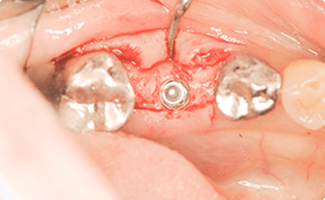

昔ぶつけた歯が揺れている

BEFORE

AFTER

症例概要

年代・性別

50歳代 女性

主訴

前歯を綺麗に治したい

治療内容

上顎両側1番CADCAM冠(根管治療)、上顎右側2番インプラント治療(抜歯即時インプラント)

治療期間

4ヶ月

治療のリスク

骨が少ない場合や膿の大きさが大きい場合は同時にできない場合があります。

治療費用

506,000円(税込)